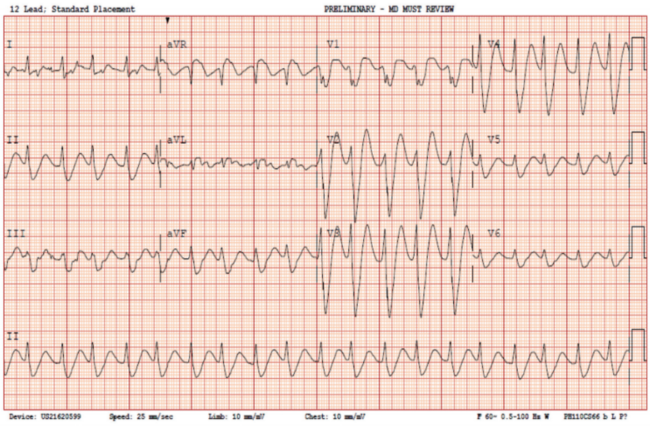

Upon presentation to the ED, he was hemodynamically stable, but his electrocardiogram (ECG) demonstrated a regular, wide complex tachycardia (Figure 1). His presenting rhythm was interpreted in the ED as ventricular tachycardia (VT), prompting treatment with amiodarone; however, cardioversion was deferred.